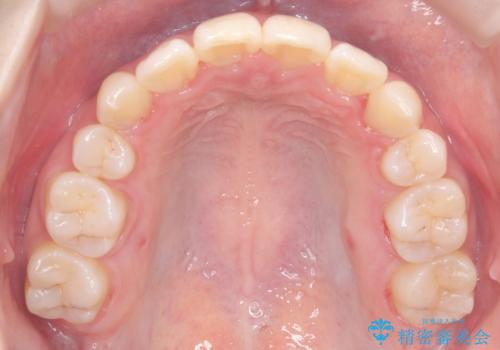

- 患者様は下顎の前歯が3本しかないという特異な歯列を持ち、噛み合わせのバランスが崩れていました。上下の歯の本数が通常と異なるため、抜歯部位の選定が重要となるケースでした。診査の結果、歯の位置や咬合のバランスを考慮し、上顎の両側小臼歯2本と左下の小臼歯1本を抜歯することで、上下の噛み合わせを整える方針としました。矯正装置は、**目立ちにくいハーフリンガル(上顎は裏側矯正・下顎は表側矯正)**を採用しました。

まず、計画通りに抜歯を行い、歯列のスペースを確保しました。上顎は裏側矯正(リンガル)で目立たないように配慮しながら歯を後方へ移動し、下顎は表側矯正を使用して、3本の前歯の位置関係を調整。上下の歯の噛み合わせを細かくコントロールしながら、全体のバランスを整えました。治療後は「歯並びがきれいになり、噛み合わせもしっかり合うようになった」と患者様にも満足していただけました。